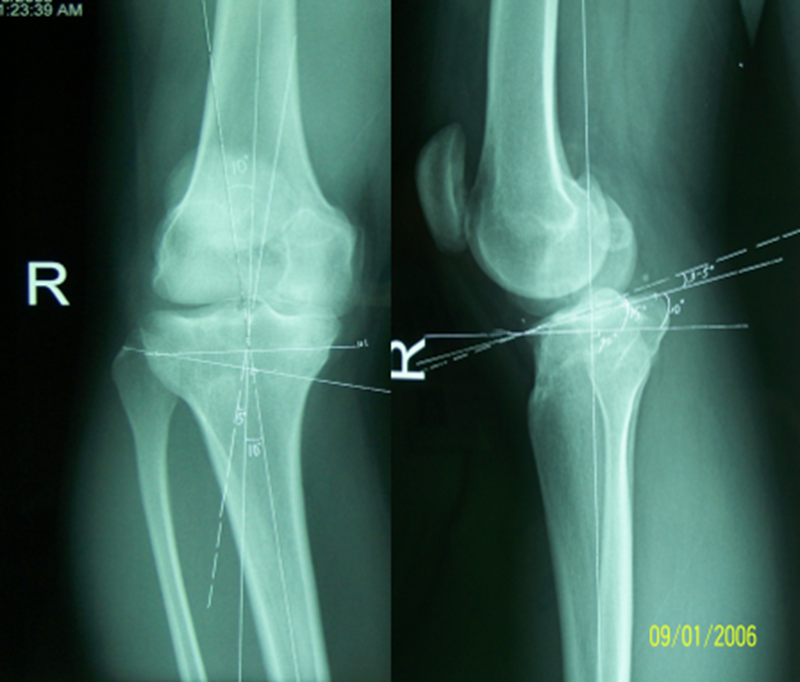

病例2:男性,19岁,因发现右膝关节内翻、过伸畸形伴跛行5年(左侧膝关节也有类似畸形,暂时无症状)。于2006年7月就诊,其母亲也有类似病史。查体:右膝关节内翻畸形约15度,应力下过伸约20度,内翻及外翻时膝关节均有松动感,Lanchman试验(+)。无负重下X片示:右膝关节内翻畸形约15度,胫骨平台无后倾,倒呈前倾13º。膝关节MR示:右膝内侧股骨及胫骨软骨面已有缺损并囊性变。诊断:先天性膝关节内翻畸形(Blount病)。

术前X线可见右膝关节内翻畸形约15°,胫骨平台前倾畸形13°

应力位过伸畸形明显